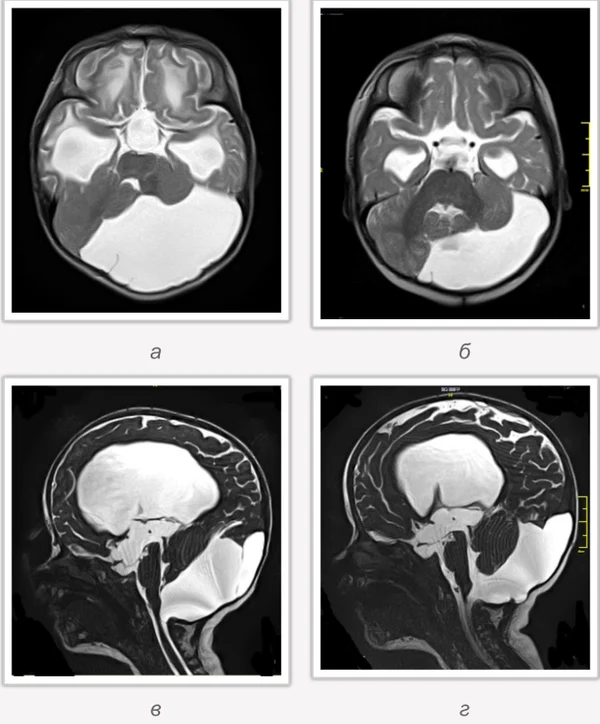

кисты, аномалии Денди-Уокера и др.Операции при внутричерепных кистах. В основном встречаются арахноидальные кисты различных локализаций и кисты сосудистых сплетений боковых желудочков. Пациентам с врождёнными кистами операции проводятся в следующих ситуациях: увеличении объема кисты в динамике, наличии клинических проявлений, компрессии и дислокации мозговых структур, наличии окклюзии ликворных путей. Нами используются 2 способа хирургического лечения кист: эндоскопическая перфорация стенок кист и открытая резекция кист. Открытая резекция кист проводится при ретроцеребеллярных арахноидальных кистах (рис. 2), при арахноидальных кистах межполушарной щели при отсутствии непосредственного контакта их стенок со стенками расширенных желудочков головного мозга и повторного увеличения кист средней черепной ямки после эндоскопической кисто-цистерностомии. Техника операции заключается в проведение краниотомии и максимальном иссечении стенок кист с созданием широкого сообщения кист с субарахноидальным пространством. Эндоскопические операции проводятся при арахноидальных кистах межножковой и пинеальной цистерн, арахноидальных кистах межполушарной щели при тесном контакте их стенок со стенками расширенной желудочковой системы (рис. 3), первично при арахноидальных кистах средней черепной ямки, а также при кистах сосудистых сплетений боковых желудочков. При арахноидальных кистах межножковой цистерны эндоскопически проводится перфорация стенок кисты, сообщая ее с просветом III желудочка и межножковой цистерной – эндоскопическая вентрикуло-кисто-цистерностомия (рис. 4). При арахноидальных кистах пинеальной цистерны проводится перфорация кисты в передне-верхних её отделах с созданием сообщения полости кисты с просветом III желудочка – эндоскопическая кисто-вентрикулостомия. С целью предотвращения облитерации сформированного отверстия иногда в полость кисты под контролем эндоскопа вводится стент перфорированный на протяжении (рис. 5, 6). Эндоскопическая кисто-цистерностомия выполняется при арахноидальных кистах средней черепной ямки. При этом создается широкое сообщение кисты с базальными цистернами. При кистах сосудистых сплетений боковых желудочков проводится их вскрытие в просвет боковых желудочков – эндоскопическая кисто-вентрикулостомия. При множественных кистах проводится их хирургическое сообщение между собой – интеркистосмия